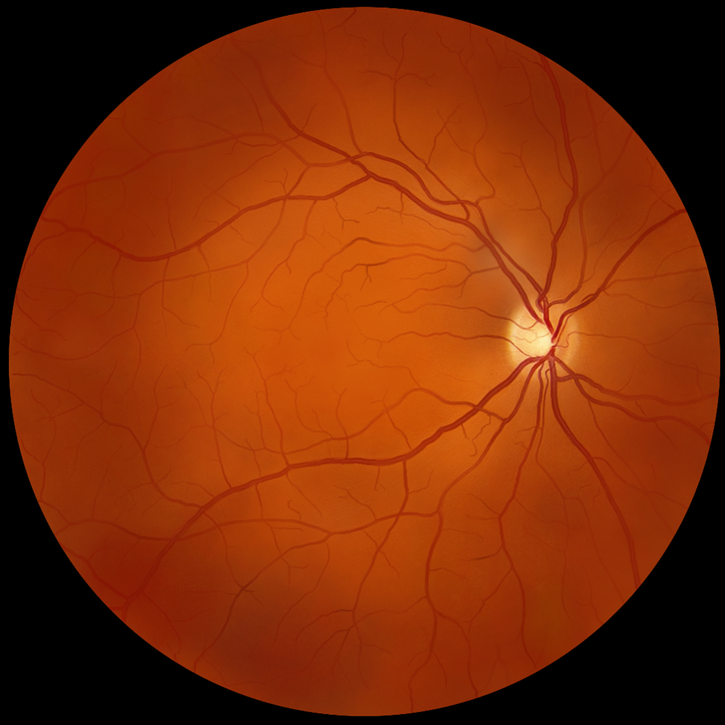

“迪视微锋”首例临床应用

眼科手术机器人的研发对于解决眼底和显微手术中的痛点至关重要。迪视医疗凭借其个性化的医工结合、基于主从控制的多自由度和独创的柔性结构技术,成功实现高达3微米的运动精度。公司在产品技术和研发进度方面保持全球领先地位。自2023年7月“迪视微锋”眼科手术机器人在浙江省人民医院完成亚洲首例人体临床应用病例后,已成功完成多例科研临床病例,术后效果良好。目前,公司正式启动NMPA注册的临床试验工作,以进一步验证其产品的安全性和有效性。此外,公司的显微外科手术机器人也已进入样机开发阶段,标志着迪视医疗在医疗机器人领域不断推进创新,为未来的医疗技术发展做出贡献。